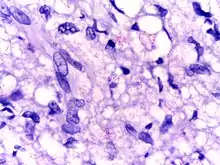

Mycobacterium leprae is an intracellular, pleomorphic, non-sporing, non-motile, acid-fast, pathogenic bacterium.[3] It is an aerobic bacillus (rod-shaped bacterium) with parallel sides and round ends, surrounded by the characteristic waxy coating of mycolic acid unique to mycobacteria. It is Gram-positive by Gram staining, but Mycobacterium leprae was traditionally stained with carbol fuchsin in the Ziehl–Neelsen stain. Because the bacilli are less acid-fast than Mycobacterium tuberculosis (MTB), the Fite-Faraco staining method, which has a lower acid concentration, is used now.[9][10] In size and shape, it closely resembles MTB. The bacteria are found in the granulomatous lesions and are especially numerous in the nodules. This bacteria often occur in large numbers within the lesions of lepromatous leprosy and are usually grouped together as a palisade.[6] By optical microscopy of host cells, Mycobacterium leprae can be found singly or in clumps referred to as "globi", the bacilli can be straight or slightly curved, with a length ranging from 1–8 μm and a diameter of 0.3 μm.[11] The bacteria grow best at 27 to 30 °C, making the skin, nasal mucosa and peripheral nerves primary targets for infection by Mycobacterium leprae.[12]

The second form of leprosy is the "lepromatous" form, in which the microbes proliferate within the macrophages at the site of entry, and has many detectable bacilli (multibacillary).[43] They also grow within the epithelial tissues of the face and ear lobes. The suppressor T-cells that are induced are numerous, but the epithelioid and giant cells are rare or absent. With cell-mediated immunity impaired, large numbers of Mycobacterium leprae appear in the macrophages and the infected patients develop papules at the entry site, marked by a folding of the skin. Gradual destruction of cutaneous nerves lead to what is referred to as "classic lion face." Extensive penetration by this bacterium may lead to severe body damage; for example the loss of bones, fingers, and toes.[44]